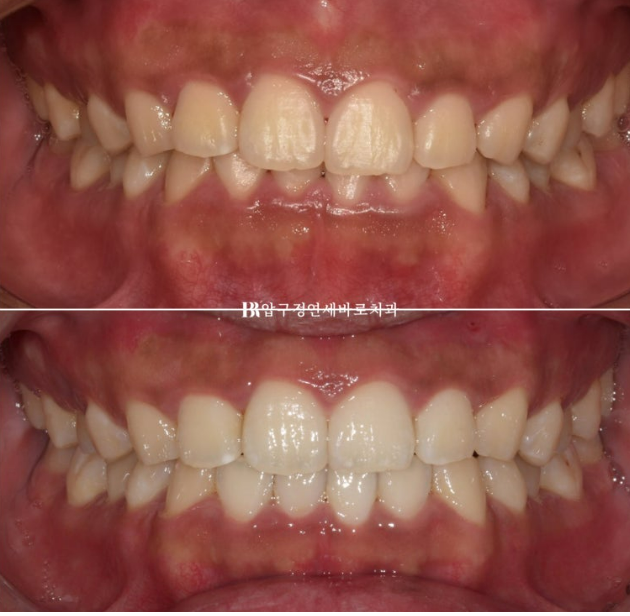

When smiling, the left teeth appear to come down lower.

The patient came in for orthodontic treatment for that reason.

When the upper teeth cover the lower teeth too much, it is called a deep bite.

The lower teeth are barely visible.

In the actual smiling photo, you can see that the occlusal plane is tilted.

The patient’s left teeth are positioned lower.

The bite after wearing all 14 aligners for 4 months.

The patient diligently wore the elastics in the blue-arrow area, and over 4 months the tilted occlusal plane and deep bite were successfully corrected.

When smiling, one side no longer appears to come down lower.

The result was good and the patient was satisfied, so treatment was completed without remaking the aligners.

24.02-24.07

As the deep bite was relieved, the lower teeth are now visible when biting down.